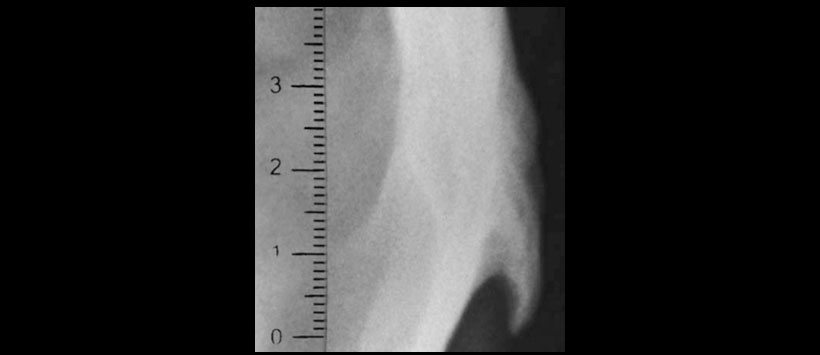

Se solicita radiografía lateral de columna cervical, abarcando cráneo (Figura 1) observando entesofito en la inserción del ligamento nucal a nivel de su inserción occipital (Figura 2).

Es un hallazgo frecuente en el género masculino, por lo que un espolón occipital prominente se usa a menudo en la determinación del sexo en las investigaciones forenses. Singh menciona que es más notorio en trepadores de árboles y jugadores de baloncesto y voleibol. A la protuberancia occipital externa se le considera de tres tipos, el tipo I es una prominencia ligera; el tipo II presenta forma de cresta; el tipo III, forma de espina (espolón). El estudio de Shahar y Sayers2 en 218 radiografías laterales de columna cervical en individuos entre 18 y 30 años de edad (108 hombres y 63 mujeres) todos asintomáticos, que clasificaron a la POE como agrandada cuando su dimensión es ≥ 10 m, reporta prevalencia de 67.4% en hombres y 30.3% en mujeres.

La EOP tipo III es un hallazgo inusual en el género femenino, reportada sólo en 4.2%. El espolón occipital, a pesar de ser una variante normal, puede volverse sintomático y originar dolor occipital y cervical especialmente en decúbito dorsal o al efectuar movimientos del cuello; algunos pacientes, especialmente aquéllos con cabello corto, pueden quejarse de que es antiestético, la resección de la hiperostosis3 y el alisamiento del hueso mejoran los síntomas, así como la estética